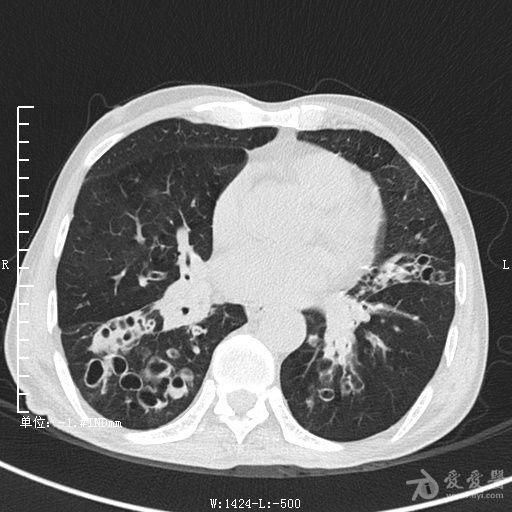

典型支气管扩张及肺水肿CT片

典型支气管扩张肺水肿